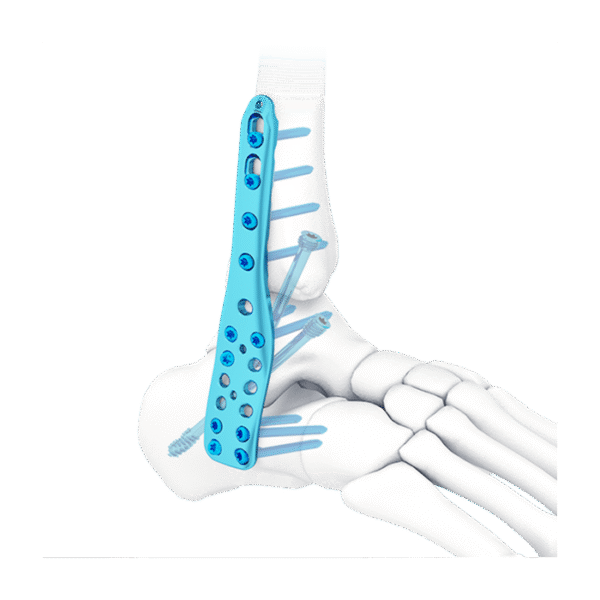

- Tres filas de orificios en el extremo distal, para fijar el calcáneo; Tornillo de fijación divergente, para mejorar la buena sujeción.

- Tres filas de agujeros en el medio, para fijar el astrágalo; tornillo de fijación divergente, para proporcionar una fijación estable

- Diseño de perfil bajo, para reducir la irritación de los tejidos blandos.

- Fusión de la articulación tibiotalar

- Fusión de tibiotalar lateral y calcáneo